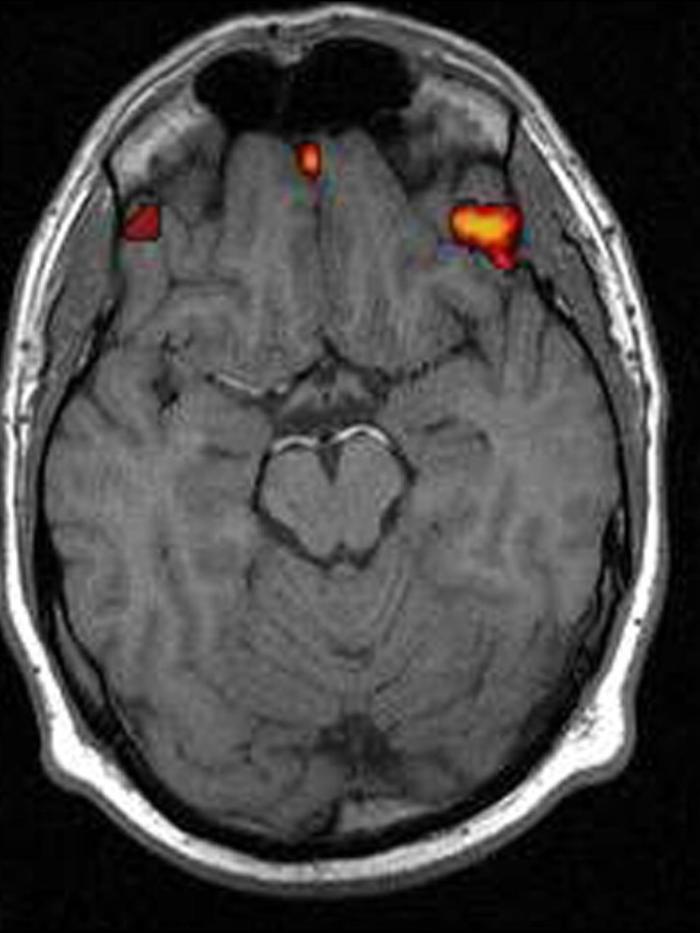

ROMA, 17 APR - Trovata nel cervello la culla della schizofrenia, ossia l'insieme delle aree coinvolte nelle distorsioni della percezione tipiche della malattia. La scoperta, pubblicata su Neuroimage: Clinical, è del Centro per i sistemi di neuroscienze e cognitivi (Cncs) dell'Istituto Italiano di Tecnologia (Iit) a Rovereto. "E' il primo passo per programmare terapie farmacologiche più mirate", ha detto il coordinatore del gruppo di ricerca, Angelo Bifone. La ricerca italiana contraddice la teoria finora più accreditata, per la quale allucinazioni e alterazioni della percezione hanno origine nella corteccia frontale, l'area del cervello che controlla le funzioni cognitive elevate come il linguaggio e la programmazione di azioni.